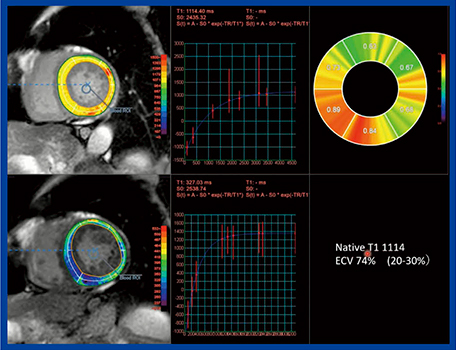

MRIでは,遅延造影(LGE)の感度,特異度がいずれも86%であり,正常心筋壁厚の患者でも早期の異常としてとらえることができる。また,LGEの程度は心不全の重症度とも相関する。LGEの画像所見としては,全層性はAL型よりもATTR型に多く見られ,全層性のAL型は予後不良である。最近ではソフトウエアを用いた定量評価が進んでおり,ECVやnative T1が予後評価に有用で,ECV45%以上,native T1が1044ms以上で予後不良とされている。図2は,80代,男性の心アミロイドーシス症例のZiostation2の「MR心筋T1マッピング」による解析結果だが,native T1が1114ms,ECVは74%と高値だった。

図2 MR心筋T1マッピングを用いたnative T1,ECV解析